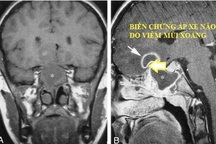

"Nhiễm trùng tai mũi họng phổ biến ở đối tượng trẻ em và thường xuyên tái phát nhiều lần. Nếu không được điều trị dứt điểm, chúng có thể gây ra các biến chứng nguy hiểm như: viêm phổi, viêm cầu thận, viêm màng não, viêm xương chũm, biến chứng nội sọ...", BS Yến cho hay.

Nhiễm trùng tai mũi họng là một trong những bệnh lý phổ biến ở trẻ em. Đây cũng là nguyên nhân hàng đầu, dẫn đến nhiễm trùng đường hô hấp và các biến chứng như: viêm phổi, viêm tim, viêm não, suy hô hấp...